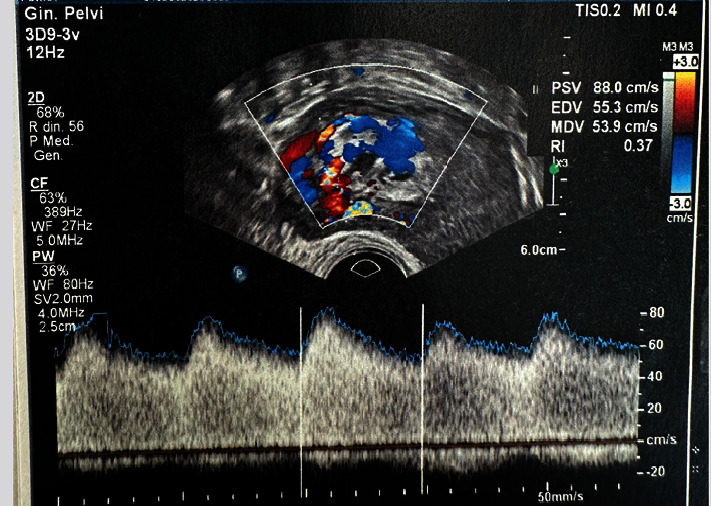

Arteriovenous malformations (AVMs) are abnormal connections between arteries and veins that bypass the capillary system. Among AVMs, uterine ones are very rare, and it is not possible to have clear data on their incidence, as a good part of the patients remain clinically asymptomatic. Uterine AVMs consist of abnormal communications between branches of the uterine artery and the myometrial venous plexus. They can lead to significant bleeding, resulting in severe anemia and the need for transfusions. Both medical and surgical therapeutic approaches are described in the literature; as regards surgical treatments, the hysteroscopic excision of the endometrial mass represents a conservative and minimally invasive approach. However, there are no reported cases in the literature of AVMs treated using a hysteroscopic approach under local anesthesia and in an office setting. In this article, we propose the case of a young woman diagnosed with postpartum uterine AVM, treated using a 16 Fr miniresectoscope (GUBBINI system; Tontarra Medizintechnik®, Tuttlingen, Germany) in an office setting with a pain control protocol (pericervical infiltration and nitrous oxide via bucconasal mask). No complications occurred, and the woman was discharged immediately after the procedure. Finally, the patient was asked how tolerable and acceptable the procedure was compared to expectations; the woman defined the procedure as very bearable and well tolerated. The outpatient treatment, with an adequate pain control protocol, proved to be less invasive for the woman, did not require narcosis and hospital admission, but was equally therapeutic and effective compared to the treatment performed in the operating room.